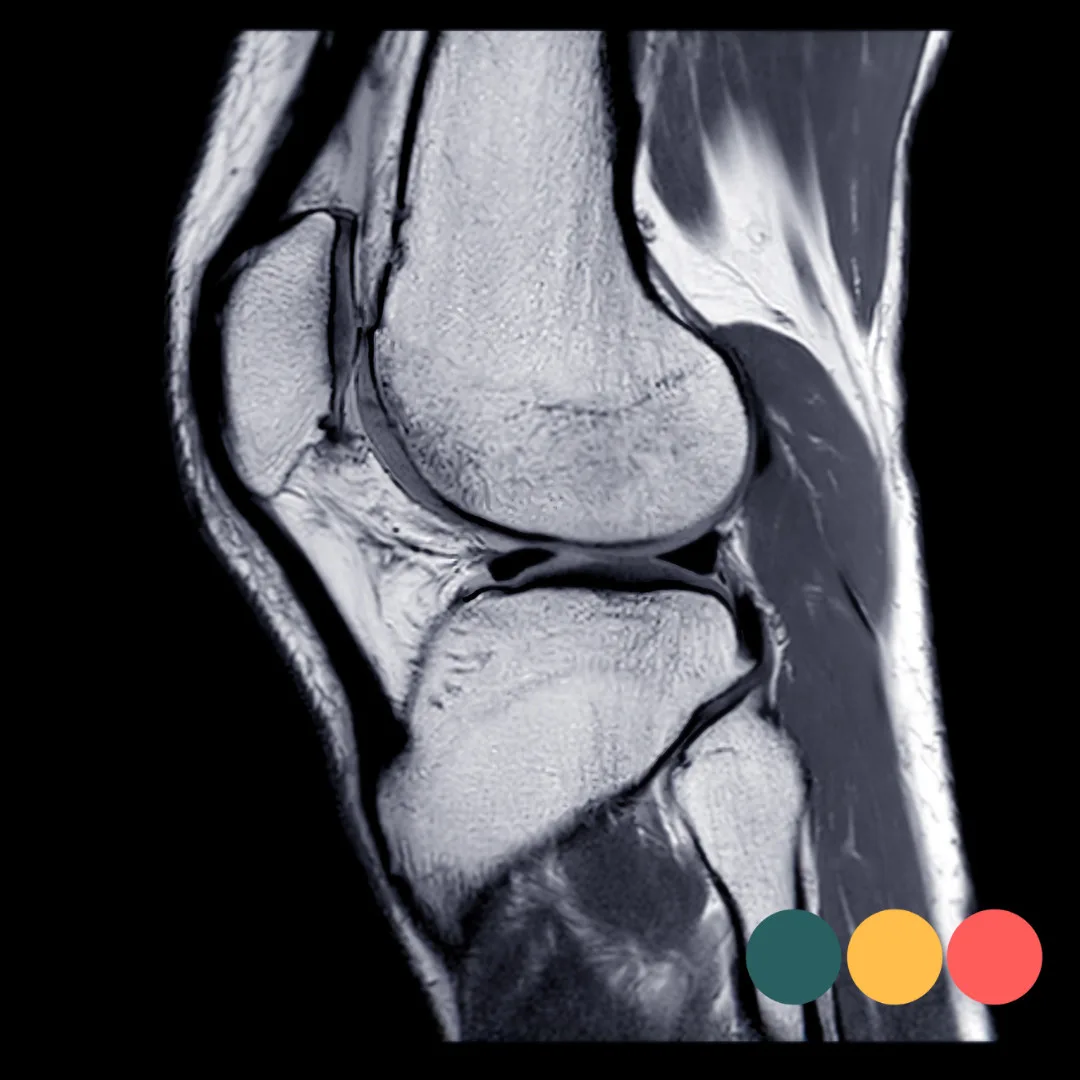

Rate of force development na een voorste kruisband blessure

Na een voorste kruisbandoperatie ligt de nadruk in revalidatie vaak op het herstellen van kracht, stabiliteit en mobiliteit. Desondanks blijven veel sporters kampen met het optimaliseren van rate of force development, zelfs wanneer zij hun maximale kracht grotendeels hebben teruggewonnen. Dit onvermogen om snel te reageren vergroot mogelijk de kans op opnieuw deze blessure. Sporten als voetbal, basketbal en hockey vereisen niet alleen kracht, maar vooral het vermogen om kracht snel te ontwikkelen. Rate of force development bepaalt of de sporter in staat is om adequaat te reageren tijdens het sprinten, springen en snelle richtingsveranderingen. Traditionele revalidaties schieten vaak tekort omdat ze onvoldoende inzicht geven in hoe snel kracht wordt gegenereerd.